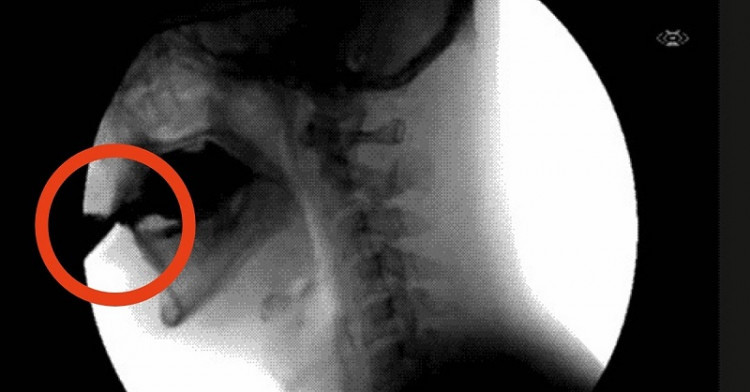

Фосфорната киселина, която се съдържа в колата, свързва калция, магнезия и цинка в долната част на червата и те се екскретират от организма в ускорен режим!

А ние получаваме недостатъчно количество от тези елементи с храната. В резултат костите стават крехки и метаболизмът се влошава.